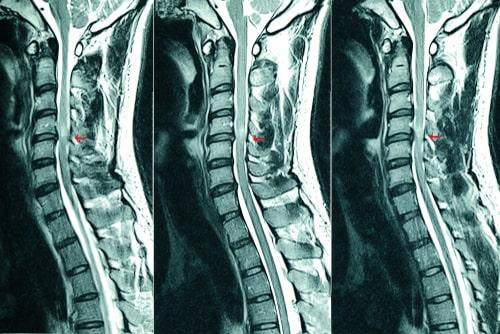

Surgical Mistakes Resulting in Spinal Cord Injury

The spinal cord transmits signals from the brain to the body and from the body to the brain. Everything from movement to our ability to sense pain is controlled by the spinal cord. Consequently, any damage to the spinal cord can have catastrophic consequences and errors during surgery on the spinal cord can leave a person permanently disabled

Accidentally nicking the spinal cord during surgery - Surgeons operating on or near the spine must use caution and precision. One small mistake can lead to devastating consequences for the surgical patient.

Incorrectly placing a surgical device or clamp - Devices like rods, screws, and clamps are often used in spinal surgeries. If these items are placed incorrectly, they can cause nerve damage or other complications.